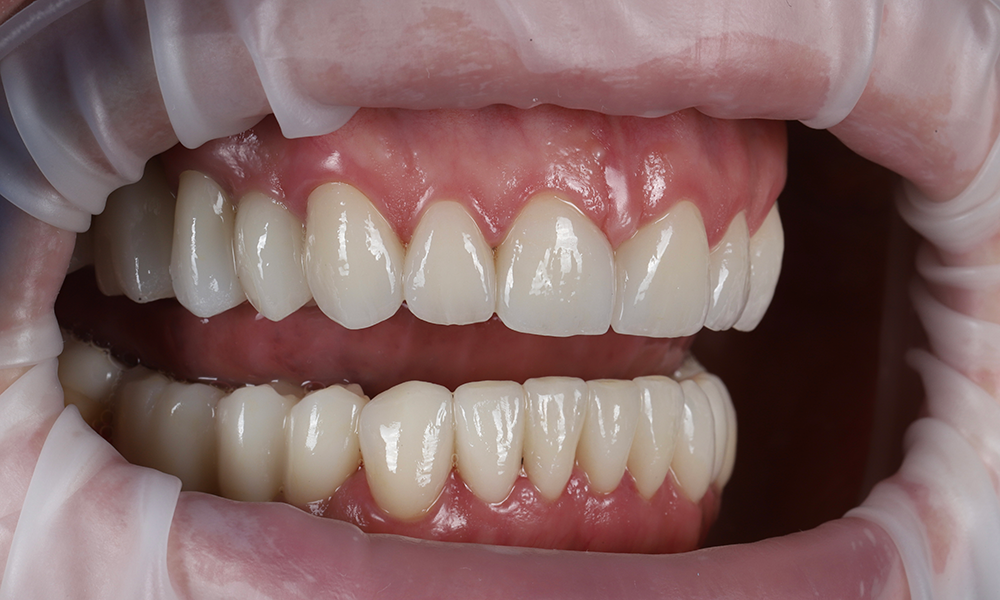

После

Результат

Улыбка пациентки — это итог большой командной работы.

Была проведена тотальная реконструкция с изменением положения и высоты челюстей, закрыты промежутки между зубами, исправлена десневая улыбка.